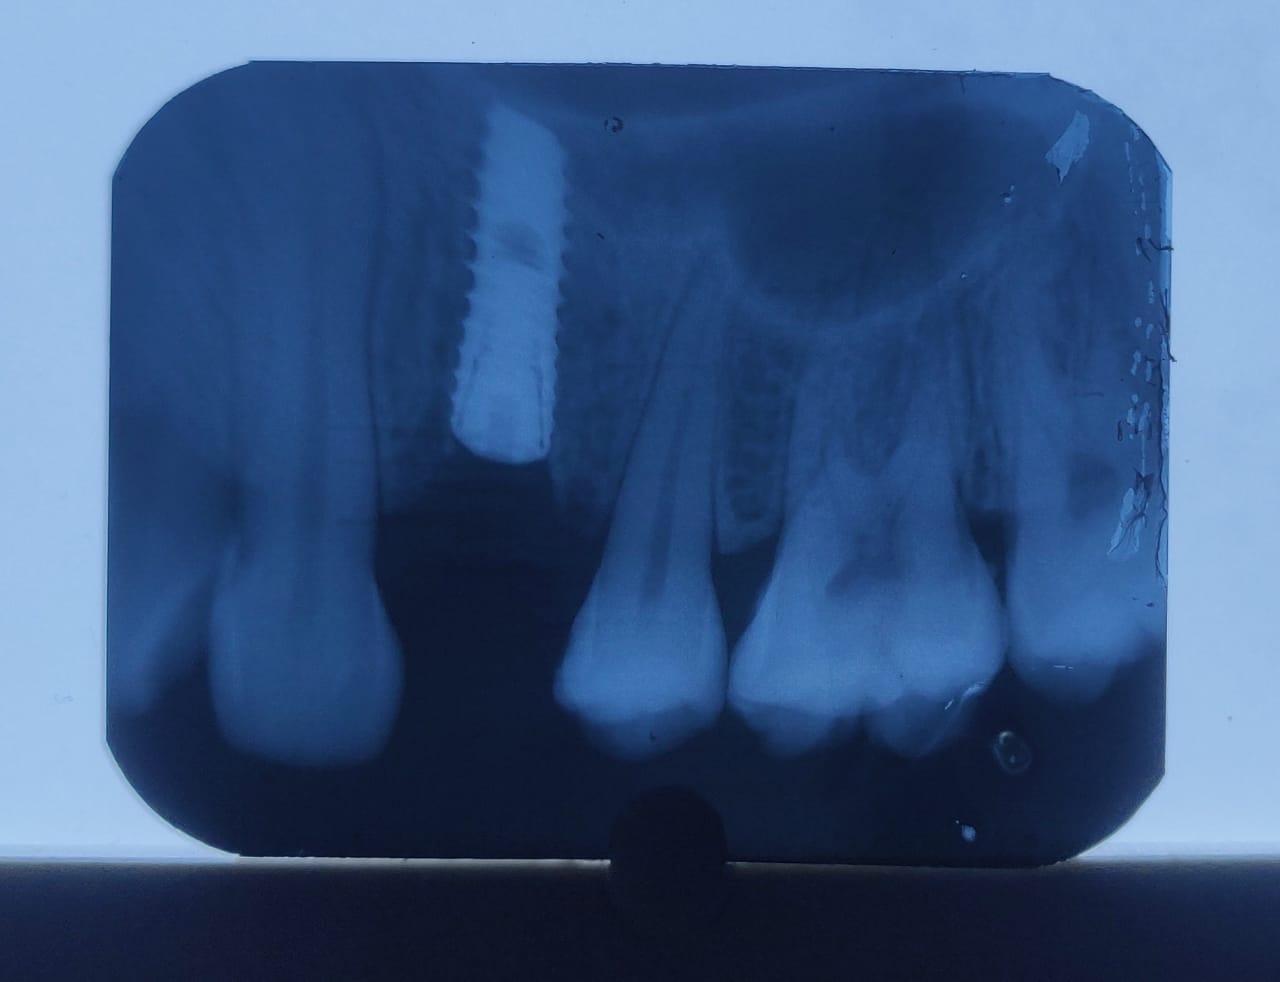

2.4 Live Surgical Demo Of Implant Placement

2.5 Implant Placement

2.6 Implant Placement

2.7 Implant Placement

2.8 Implant Placement

2.9 Implant Placement